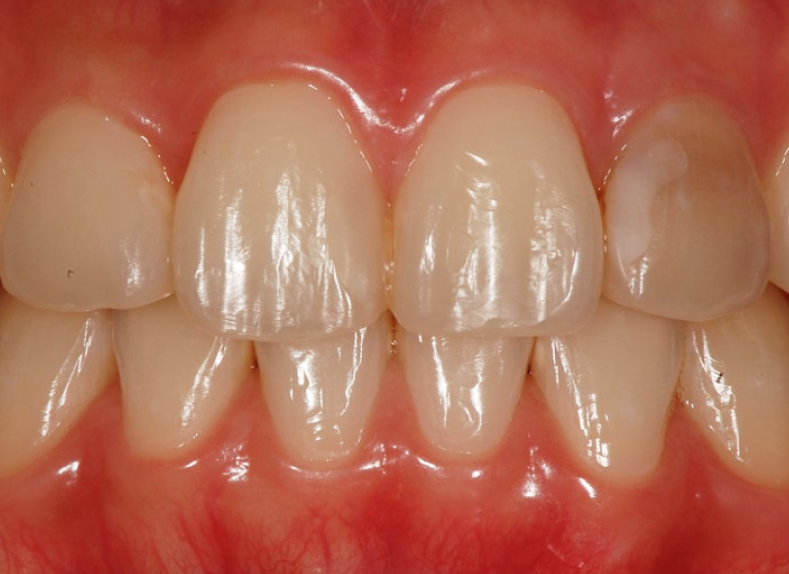

최종 크라운을 장착했을 때

변색도 해소되고

앞니 라인도 자연스럽게 정렬되어

환자분도 만족해하셨습니다.